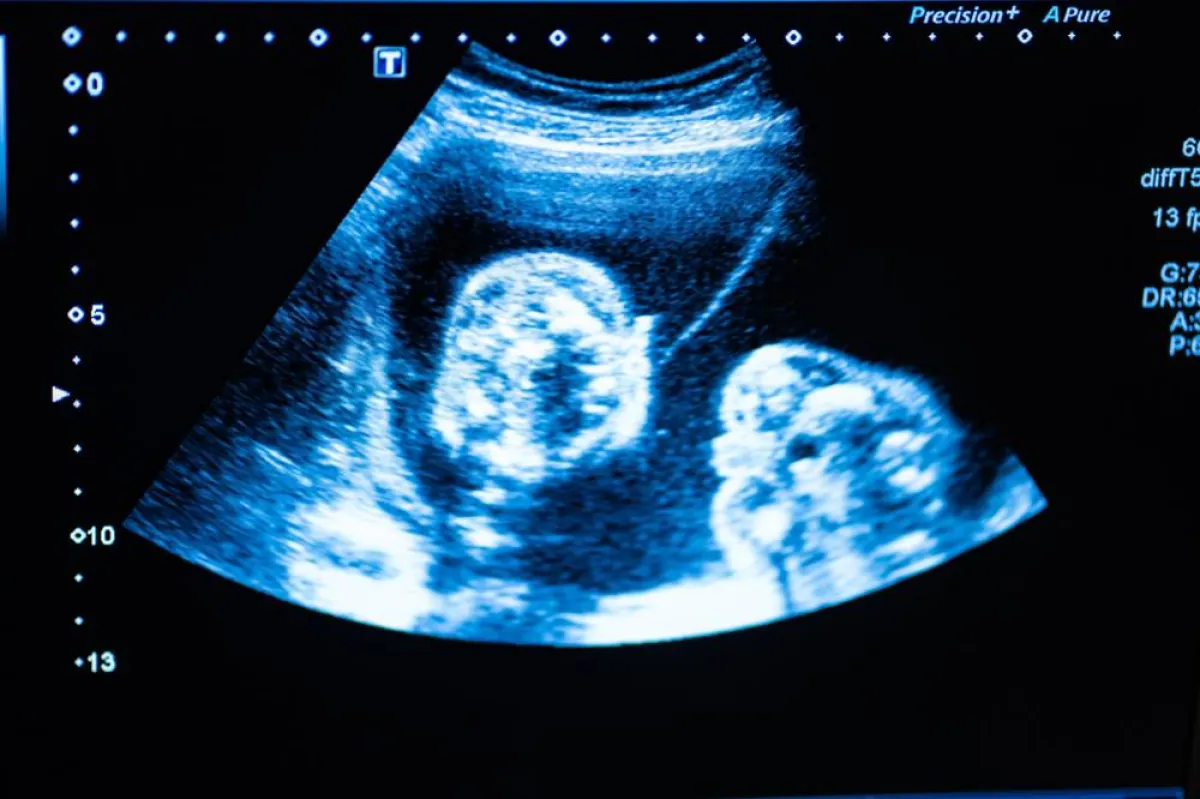

عدد المواليد: قد تكتشفين أن لديك توأم، وفي هذه الحالة، قد تحتاجين إلى برنامج عناية خاصة.

2 - يبلغ طول طفلك في هذه المرحلة حوالي ربع بوصة فقط، لذلك لن تري الكثير من التفاصيل، عليك الانتظار حتى 11 إلى 12 أسبوعاً للحصول على تحديد دقيق بنسبة 91٪ لنوع مولودك.

5 - تصوير الموجات فوق الصوتية بعد 6 أسابيع، يُظهر كيس الحمل مع كيس الصفار بداخله، والذي يوفر العناصر الغذائية للجنين الذي ينمو بداخلك.